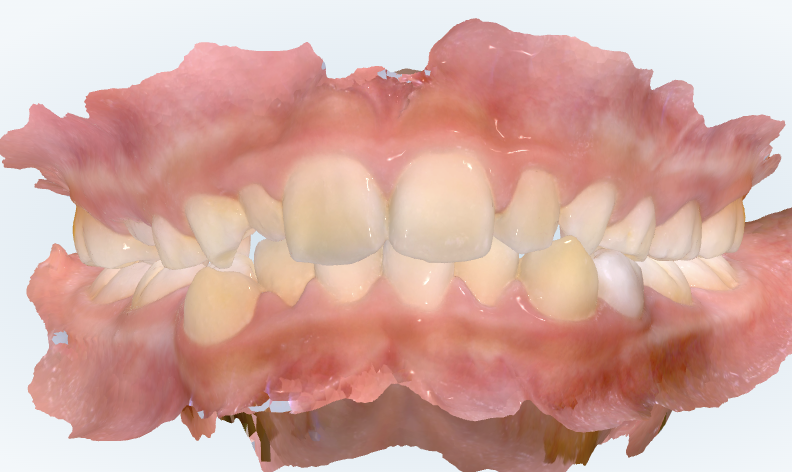

初診時の画像診断

上下の歯並びにガタガタがみられます。

右上の前から2番目の歯が小さいです。(矮小歯)

右上の前から4番目の歯が顎の骨の中で後ろに傾いています。